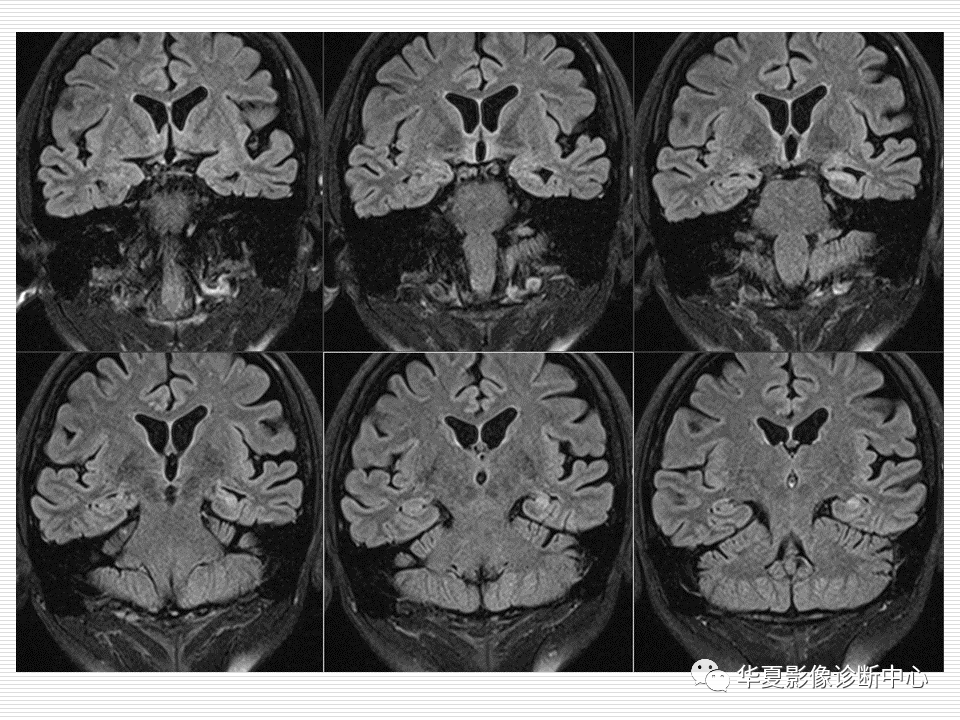

关于海马硬化的影像诊断

图片尺寸960x720